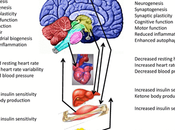

Exercise and Intermittent Fasting Improve Brain Plasticity and Health

I thought it might be useful to point to this brief review by Praag et al. that references several recent pieces of work presented at a recent Soc. for... Read more

Posted on 29 December 2014 PSYCHOLOGY, SCIENCE -